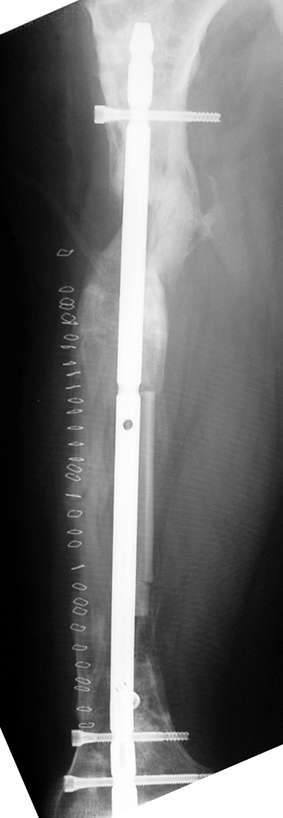

Appropriate radical debridement necessitates excision of all necrotic bone and soft tissues, and frequently causes instability at the involved extremity. The remaining bone and soft tissue defect has to be fixed and reconstructed. The distraction osteogenesis method of Ilizarov is used successfully for achievement of union, correction of the deformity, elimination of limb length inequality and reconstruction of segmental bone defects.

The duration of external fixation (external fixation index) depends on the amount of distraction required, and the extremity is prone to complications during this period. After the distraction phase is completed, the external fixator remains in place during the consolidation phase, which lasts twice as long as the distraction phase; but this period is hardly tolerated. If the external fixator is removed before sufficient consolidation is achieved, fractures, deformity and shortness will be the result. In our department, ‘lenghthening over nail’ method is used in order to decrease the external fixation index and increase patient comfort and activity level. In this method, the intramedullary nail is statically locked after the completion of the distraction phase, and external fixator is removed. The extremity is stabilized by the intramedullary nail during consolidation phase. In this way, complications due to long external fixation index or early removal of the external fixator are avoided.

Case 2